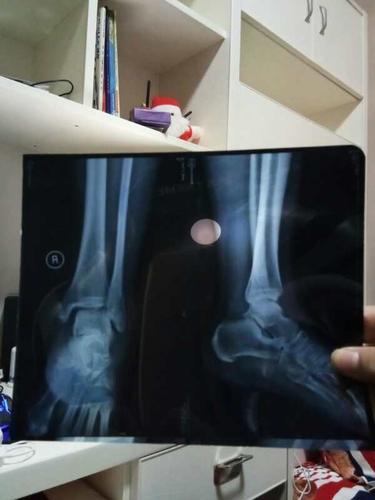

脚骨折片子,骨折片子

到医院拍了片子,医生说骨折了,片子显示右脚踝骨折两处.

脚踝骨折